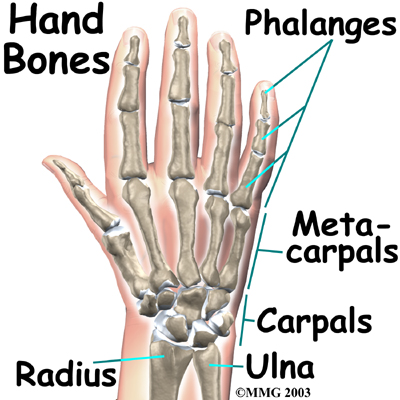

Bones and Joints

There are 27 bones within the wrist and hand. The wrist itself contains eight small bones, called . The carpals join with the two forearm bones, the radius and ulna, forming the wrist joint. Further into the palm, the carpals connect to the metacarpals. There are five metacarpals forming the palm of the hand. One metacarpal connects to each finger and thumb. Small bone shafts called phalanges line up to form each finger and thumb.